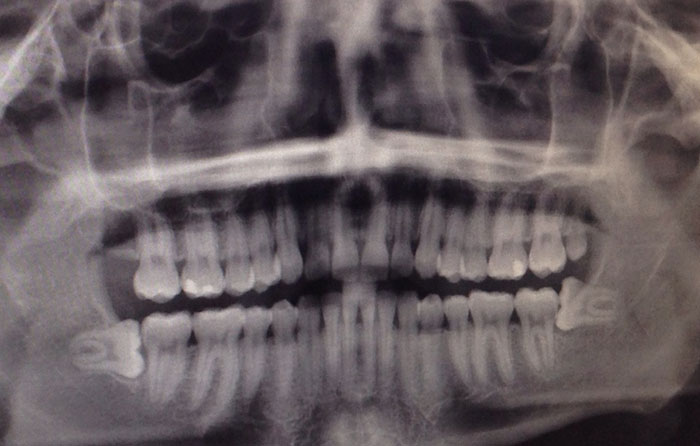

I Have A Rare Disorder Called Cleidocranial Dysotosis. Got My First Dental X-Ray Today And I Have A Lot Of Extra Teeth

Panoramic X-Ray Of A Child (Adult Teeth Growing In)